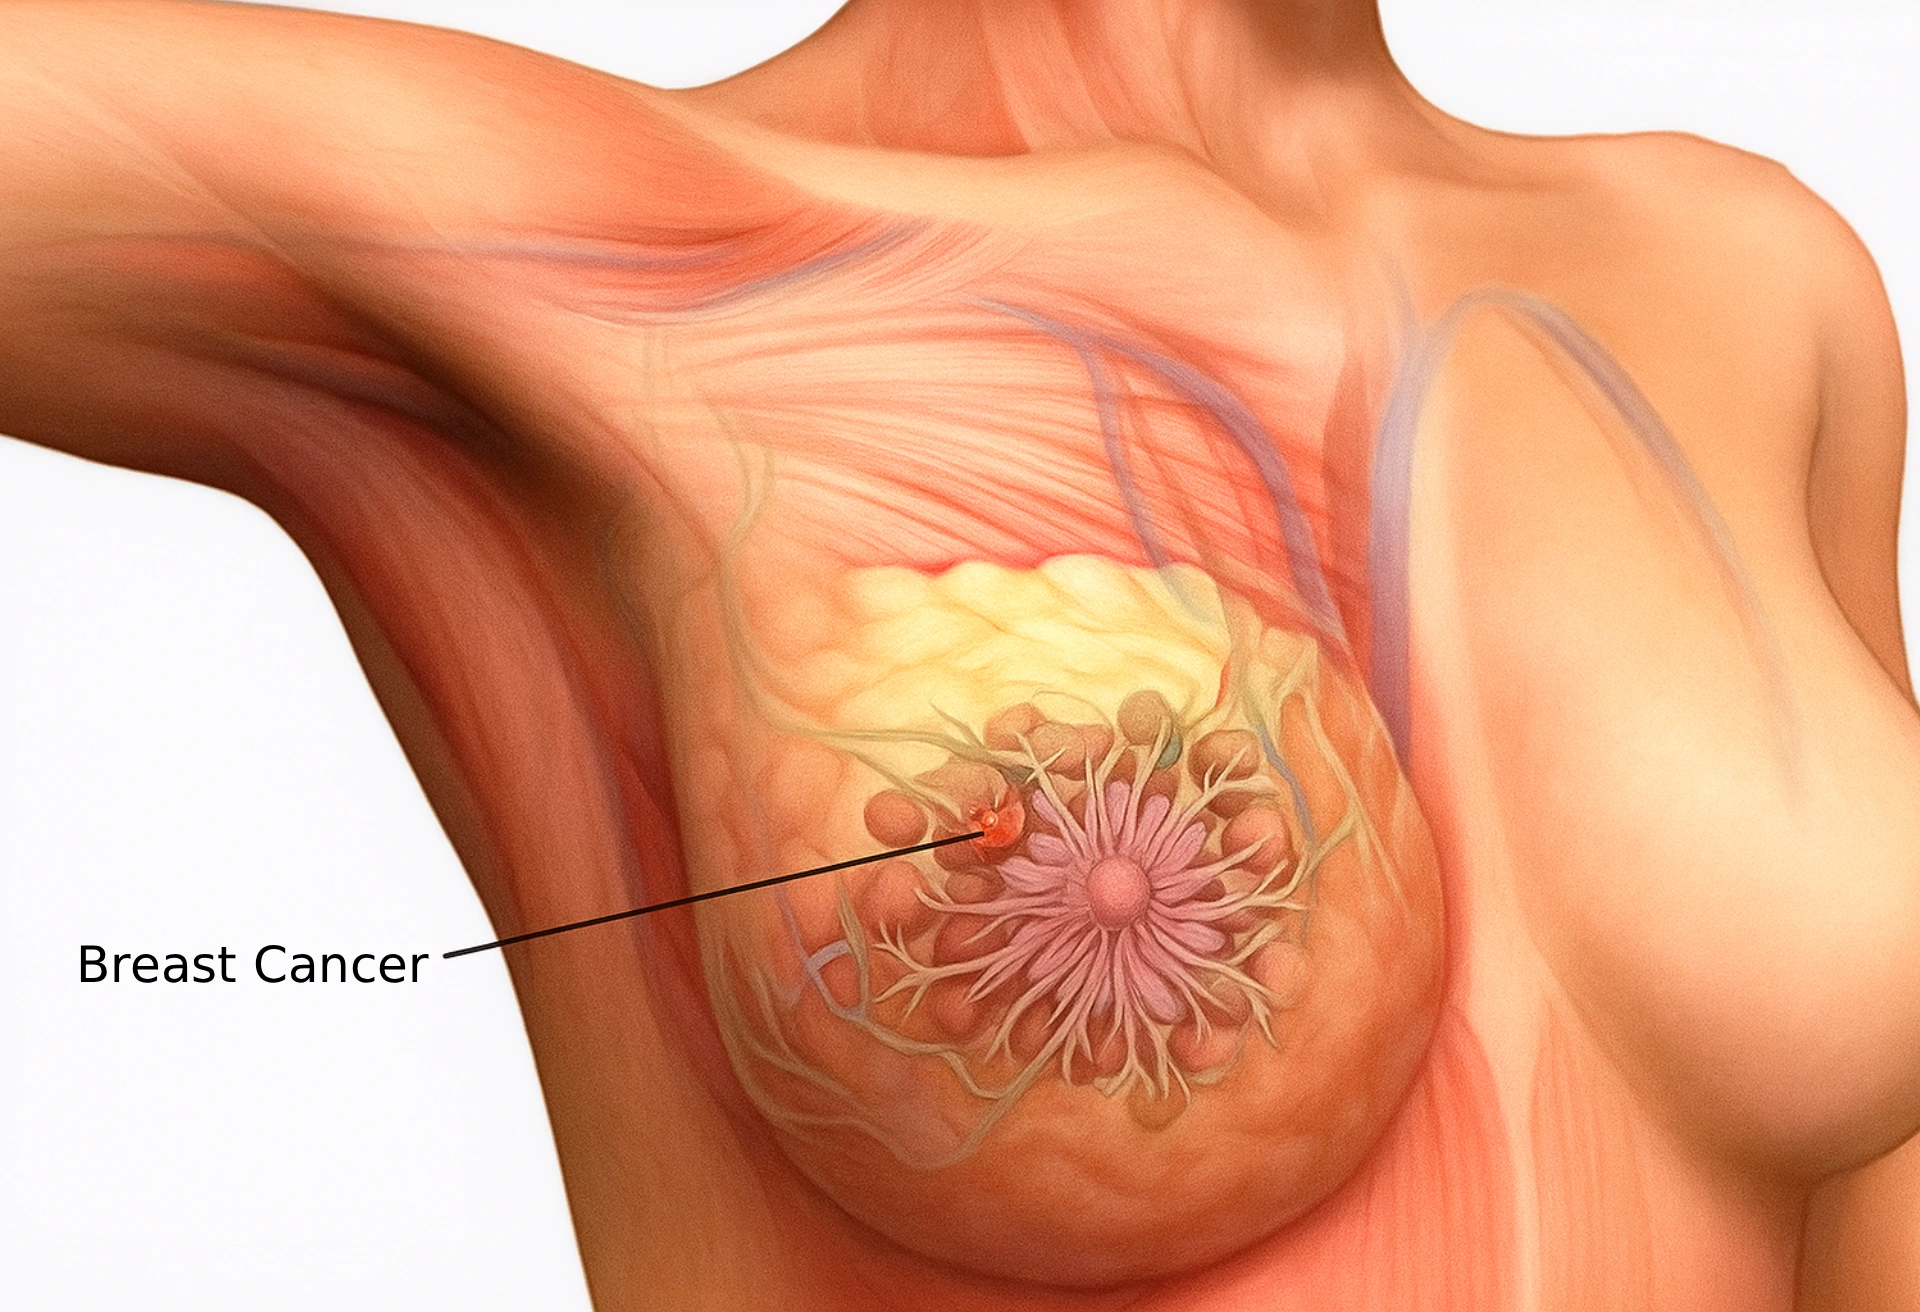

۱. سرطان پستان

سرطان پستان یکی از شایعترین سرطانها در زنان است. شناسایی زودهنگام علائم آن میتواند شانس درمان موفق را افزایش دهد.

علائم اولیه:

- ایجاد توده یا برجستگی در پستان یا زیر بغل که معمولاً بدون درد است.

- تغییر در اندازه یا شکل پستان.

- تغییر در پوست پستان مانند قرمزی، تورم یا فرورفتگی پوست (شبیه پوست پرتقال).

- ترشح غیرمعمول از نوک پستان، بهخصوص اگر خونآلود باشد.

- درد یا حساسیت غیرمعمول در پستان یا نوک پستان.

نکات کاربردی:

- خودآزمایی ماهانه پستان میتواند به شناسایی تودهها کمک کند.

- غربالگری با ماموگرافی برای زنان بالای ۴۰ سال توصیه میشود.